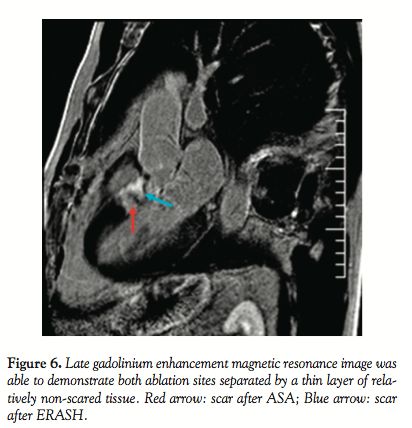

Follow-up. The patient felt well after ERASH. Continuous ECG monitoring (performed until discharge at day 8) did not reveal any atrioventricular conduction block or other arrhythmia. Maximum CK-MB mass was 1.1 µkat/L and maximum Troponin I was 3.3 µg/L (normal upper limit, 7.2 µkat/L and 0.03 µg/L, respectively). Seven days after the procedure, the ablated region exhibited similar changes of the opacity at echocardiography as at the end of the procedure, indicating damage at the ablated site (Figure 5). However SAM and LVOT gradient persisted, reaching about 50 mm Hg at rest and 100 mm Hg after nitrate provocation. The patient was therefore continued on beta-blockers. Magnetic resonance imaging (MRI) using gadolinium administration performed on day 8 after ERASH demonstrated late enhancement in two LVOT regions: the first one in the subaortic region corresponded with RF lesion sites, the second one (more midventricularly located) with scar after ASA (Figure 6). The patient was kept on his permanent medication after the procedure. At the 2-month follow-up exam, the patient reported improvement of symptoms. Dyspnea reduced to NYHA class 2 and angina CCS 1-2. Echocardiographically, the RF ablated region measured 14 mm; however, the persistent subaortic maximum was now akinetic, thus leading to a LVOT gradient reduction to 15 mm Hg. Gadolinium-contrast MRI showed findings similar to day 8 after ERASH.